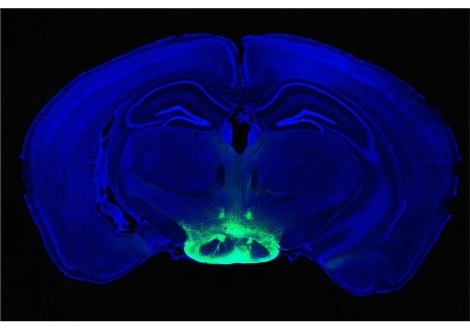

تركت النتائج مفتوحة السؤال عما إذا كانت العصبونات تساهم في سلوكيات مختلفة استجابة للسكريات مقابل المحليات الاصطناعية. للإجابة على ذلك ، لجأت المجموعة إلى علم البصريات الوراثي ، وهي منهجية تستخدم في الغالب في الدماغ. قام الباحثون بتغيير الفئران وراثيًا بحيث يؤدي التعرض لأطوال موجية معينة من الضوء إلى إسكات خلايا الأرجل العصبية التي يتم تحفيزها عادةً بواسطة السكريات والمحليات ، بينما يحفزها الآخرون ، ومع ذلك لن يكون للآخرين أي تأثير ويسجلون كيف يؤثر ذلك على تفضيلات الفئران. كانت المشكلة أن توصيل الضوء يتطلب تقليديًا كابل ألياف بصرية سيليكا صلبًا ، والذي من شأنه أن يخترق الأنسجة الرخوة للأمعاء المتماوجة باستمرار. لذلك ، تعاون الباحثون مع المهندسين لتطوير كابل ألياف بصرية مرن يتكيف مع الظروف البيولوجية الفريدة للأمعاء ، كما يقول Bohórquez.

كتب بوتلر أن تكييف التلاعب البصري الوراثي مع القناة الهضمية هو الجزء "الأكثر إثارة" من الورقة ، و "تقنية أعتقد / آمل أن تكتسب قوة دفع في مجتمع علوم الأمعاء والدماغ."

يقول Bohórquez إن الألياف الضوئية الجديدة التي استخدمها فريقه في تجاربهم مرنة ويمكن وضعها في أماكن صغيرة جدًا تتحرك باستمرار - مثل القلب والرئة - مما يمكن الباحثين من "البدء في استجواب كيف أن المدخلات الحسية من كل هذه الأعضاء تؤثر على سلوكنا ". يمكن أن "يحمل المفتاح" ، وفقًا لبوركيز ، لفهم أفضل للصحة العقلية أو المزاج أو اضطرابات النوم المرتبطة بالجهاز الهضمي.

في تجاربهم ، كان لإسكات العصبونات تأثيرات ملحوظة على سلوك الفئران. فقدت الفئران التي تعرضت لضوء إسكات الأرجل العصبية تفضيلها لاستهلاك السكر على السكرالوز المُحلي عند تقديمها مع الخيارين ، في حين أن الفئران المعرضة لطول موجة تحكم لم تفعل ذلك. علاوة على ذلك ، عندما يتم تحفيز الخلايا العصبية للفأر عن طريق الضوء ، تمت مضاعفة مدخولها من المُحلي الصناعي ، حيث يشربه الحيوان كما لو كان سكرًا.

قام الباحثون أيضًا بقياس نشاط العصب المبهم في الفئران ذات الوراثة البصرية ، ووجدوا أن ضوء إسكات العصب العصبي يلغي جميع الاستجابات من العصب المبهم ، في حين أن النشاط لم يتغير عن طريق الأطوال الموجية الضابطة.